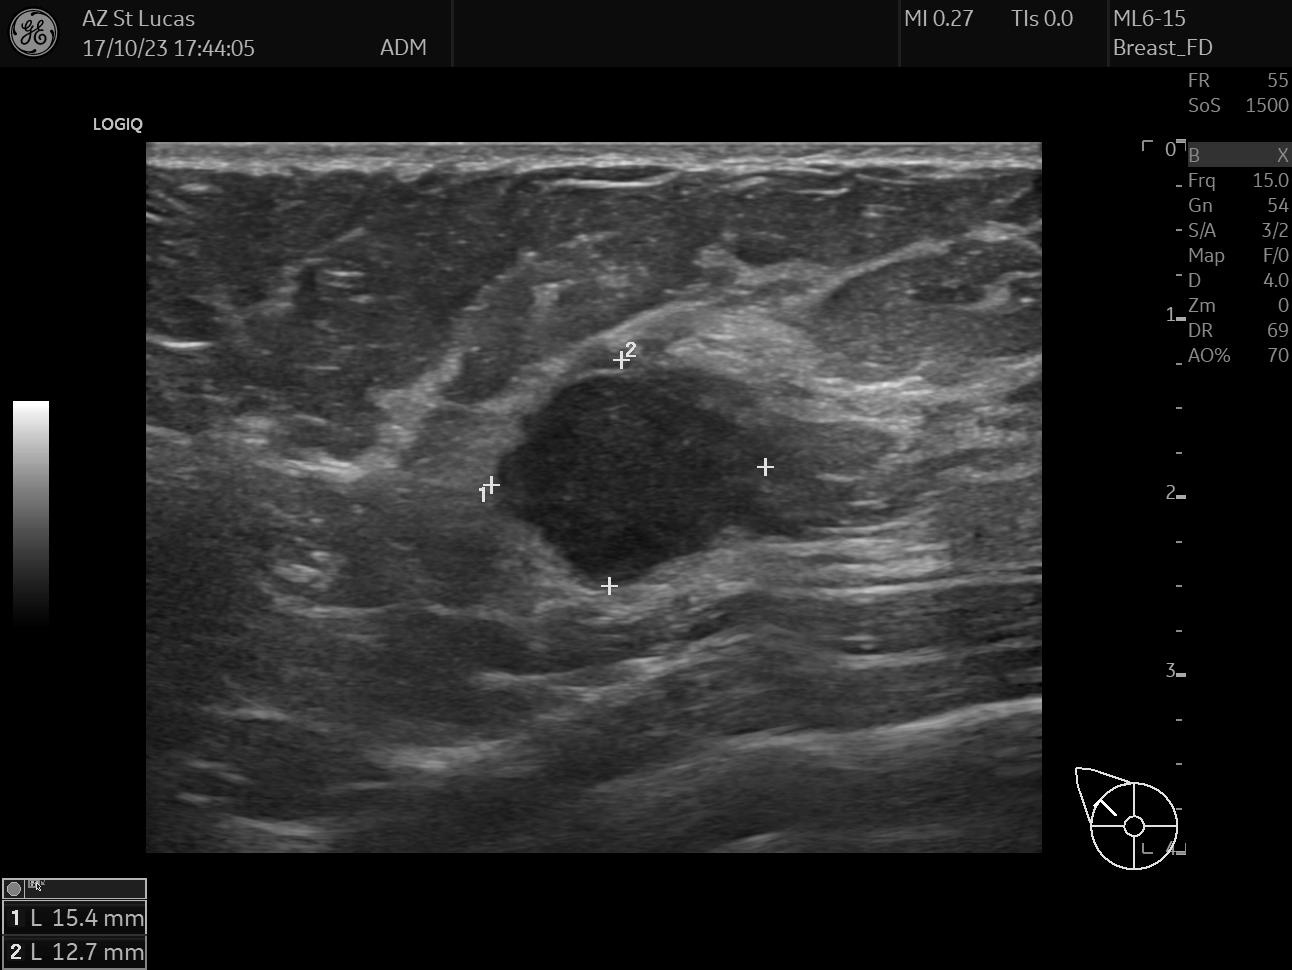

On October 17th 2023 I went to the hospital for an echography; the radiologist asked me almost immediately if they could perform a biopsy. So they stuck a needle in my breast and took out a few tissue samples. It was painful as hell and I ended up crying, confused, and trembling on the bed. The doctor asked me why I went alone for a check of this entity. Well, I didn’t know better, but there was my first lesson:

The data I chose for this day are two scans from the echography, they both clearly show the lesion; the second picture also shows the measurements the radiologist took.